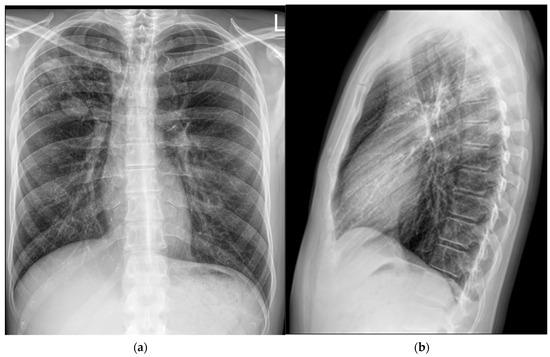

A 37-year-old man was admitted to the Division of Pulmonology, Department of Internal Medicine, Sestre milosrdnice University Hospital Center, on 25 April 2024 due to a two-month history of subfebrile temperature, malaise, productive cough, and night sweats. During the same period, he had experienced loss of appetite and an unintentional weight loss of 4 kg (BMI: 21 kg/m2). The patient had no known chronic medical conditions. He reported occasional cigarette smoking and denied alcohol or illicit drug use. Notably, he had no contact with a known TB patient but reported that his dog had died of disseminated TB six years prior. Based on the patient’s symptoms and a chest X-ray showing features suggestive of a lung abscess in the right upper lobe, his general practitioner initiated empirical antibiotic therapy with amoxicillin/clavulanate (1000 mg t.i.d.) for seven days and referred him to a pulmonologist for further evaluation (Figure 1).

Figure 1. Chest X-rays (25 April 2024). In the upper lobe of the right lung, an area of inhomogeneous opacity is observed, containing a cavity measuring 27 mm in diameter. Additionally, there are fibroadhesive and reticulonodular opacities, along with a larger soft tissue mass exhibiting nodular characteristics: (a) frontal presentation; (b) lateral presentation.